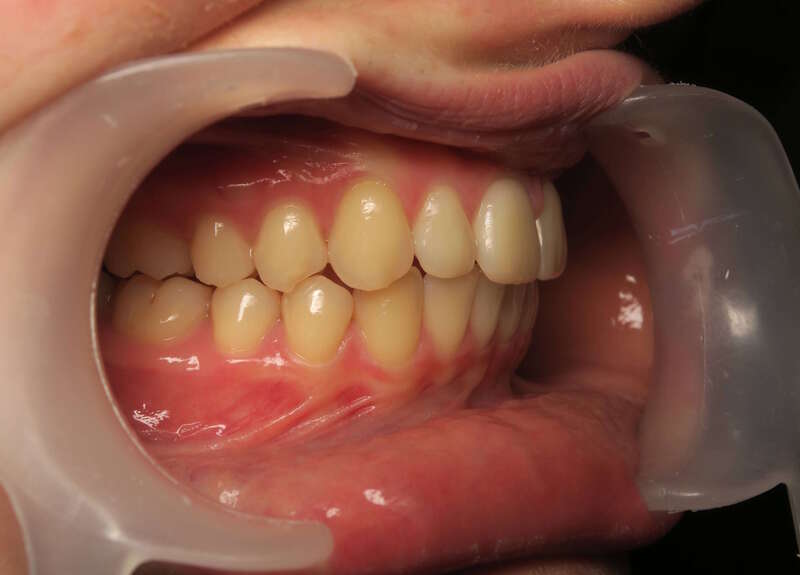

Ce cas d’interception chez un enfant de 8 ans démontre l'efficacité des aligneurs pour corriger des troubles fonctionnels précoces. Le diagnostic présentait des inversions d'articulé provoquant une déviation de la mandibule vers la gauche et un décalage des milieux.

Grâce à une coopération exemplaire et un traitement totalement indolore, l'expansion de l'arcade a permis de recentrer la mâchoire. Cette intervention a littéralement remis la croissance sur les rails, neutralisant le risque d'asymétrie faciale squelettique.

• Correction fonctionnelle : Recentrage immédiat de la mandibule et des milieux inter-incisifs.

• Prévention : Création d'un environnement favorable pour les dents définitives à venir.

C'est une étape fondamentale qui simplifie l'avenir orthodontique du patient tout en garantissant un développement facial harmonieux.